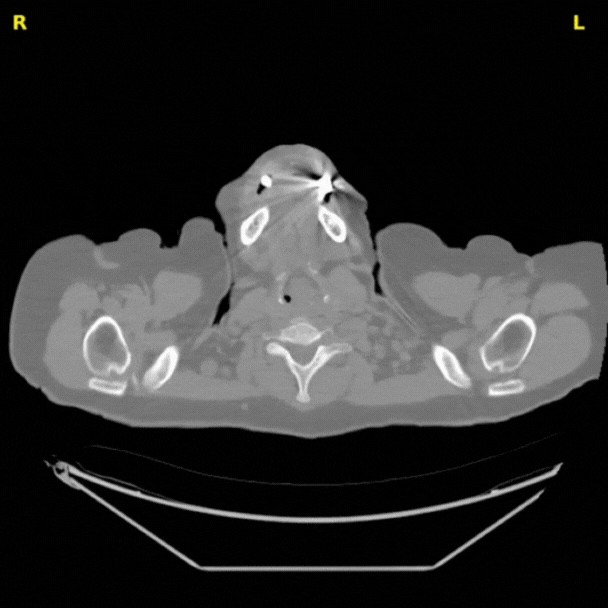

Case_Study_Precision_result2.gif

Cardiac imaging analysis pipeline

A streamlined AI workflow that processes every CT scan with accuracy and consistency.

Coronary calcium analysis

AI automatically detects, segments, and scores coronary calcium in CT images, revealing early plaque buildup and giving clinicians clearer insights into cardiovascular risk.